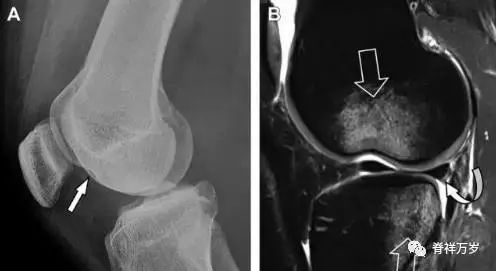

前交叉韧带撕脱骨折常发生在胫骨髁间嵴(图 1)。这种骨折在青少年中常见,但在成年人中也并不像大家想象的那么少见。

图 1 摩托车事故患者前交叉韧带撕脱性骨折

A 正位片示胫骨髁间嵴底部骨折(箭头),注意别把这个骨折碎片错认为关节内结构。B 侧位片示胫骨上方可见一细长型骨折碎片(椭圆)。C MRI 矢状位 T2 加权像示前交叉韧带附着于撕脱的骨折碎片上(箭头),注意周围存在骨髓水肿和积脂血征(空箭头)。